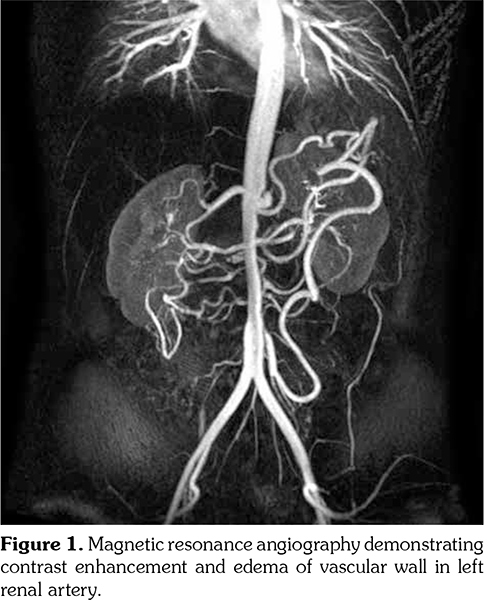

Case 3- A 33-year-old female patient was diagnosed of TA in 2013 with complaints of malaise, anorexia, systolic blood pressure difference, high ESR (120 mm/hour) and CRP (79 mg/L), and type V angiographic involvement. MTX and 1 mg/kg MP were prescribed at the beginning of treatment. Because of gastric intolerance, MTX was changed to LEF. We tapered MP dose gradually. With 15 mg/day dose of MP, we observed elevation of ESR (80/hour) and CRP (58 mg/L) with complaints of weakness, malaise, and fever. On control MR angiography, a new finding, narrowing of left renal artery that involved 8.5 cm segment with contrast enhancement and edema of vascular wall, was observed. Patient had plans of conception. So, LEF was discontinued and cholestyramine wash-out procedure was initiated and control LEF level was studied. Due to the progression of disease and wish for pregnancy, CZP was initiated. She was treated with CZP for 12 months and MP dose was tapered to 5 mg/day. At one year of CZP treatment, she was still in laboratory (ESR: 26 mm/hour, CRP: 3 mg/L) and clinical remission (no onset of hypertension or no constitutional symptom). Although there was no further narrowing of left renal artery, contrast enhancement and edema of vascular wall that involved 8.5 cm segment in left renal artery were re-observed on control MR angiography (Figure 1). Because of clinical and laboratory remission with good physician’s and patient’s global assessment, CZP treatment was continued.